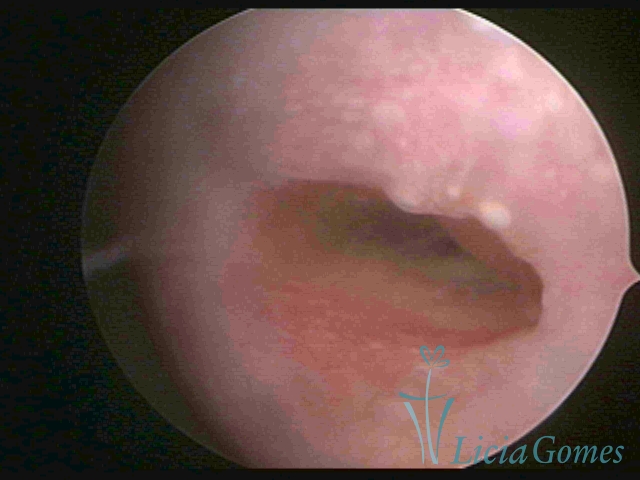

Primeira porção ou setor proximal ou setor inferior:

Durante a fase proliferativa, encontramos muco claro e cristalino pouco aderente à óptica. As criptas e as papilas apresentam-se um pouco edemaciadas e vascularizadas, micro vesicular, lembrando cachos de uva.